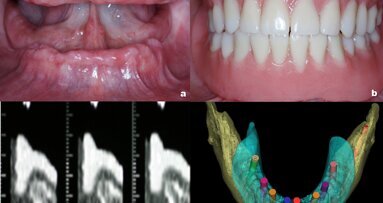

Este artículo afirma que la precisión y facilidad para transferir tratamientos diseñados virtualmente a la condición ...